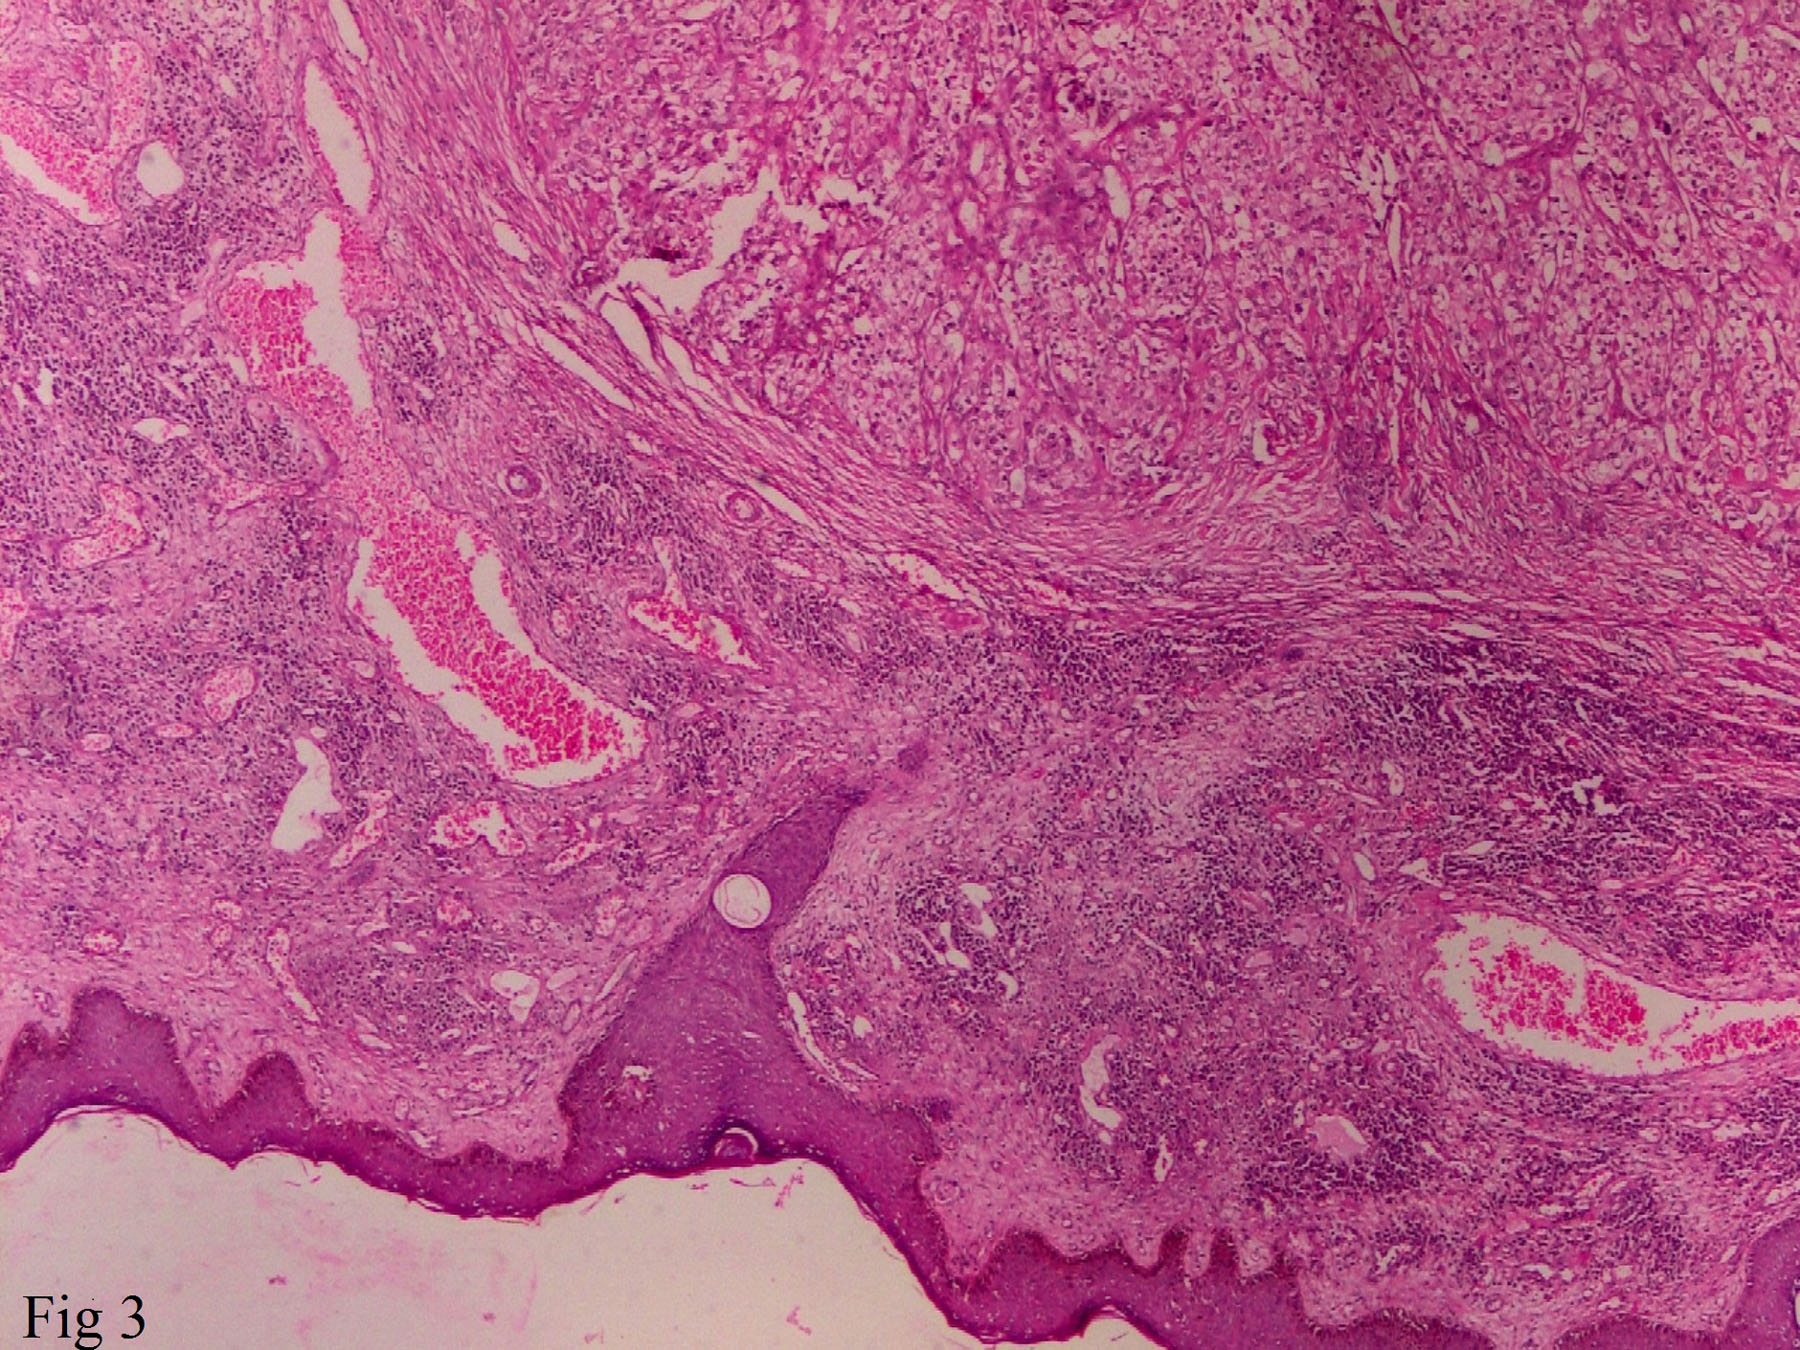

A 51-year-old male presented with a solitary, painless irregular swelling over chin for 3 months. On examination the swelling was firm, measuring about 3x2x1cm. No other significant past history was given at this point. Computed Tomography (CT) scan of face and neck showed a solitary well defined heterogenously enhancing mass arising from skin and subcutaneous tissue measuring 27x17x15mm in size. Radiological impression was of a primary skin tumour or metastatic tumour. FNAC was done and slides stained with May Grunwald Giemsa (MGG), Haematoxylin and Eosin (H&E) Papanicolaou (Pap) stain. Smears prepared from the swelling were moderately cellular and showed predominantly large singly scattered cells with few clusters of poorly cohesive cell. Cells showed an abundant pale, foamy/vacuolated cytoplasm with central to eccentric nucleus, 0-2 nucleoli and bland chromatin [Table/Fig-1]. In some cells, nuclei were totally or partially stripped of cytoplasm leaving bare nuclei [Table/Fig-2]. No intranuclear cytoplasmic inclusions were noted. Based on smear examination, a diagnosis of “clear cell malignant tumour, possibly metastatic RCC” was made. On second visit of patient detailed questioning was done with review of past records. History of nephrectomy 11 years back was elicited. Wide excision of tumour was done and sent for histopathology. On histopathological examination it was confirmed as metastatic RCC-clear cell type showing the typical clear cells arranged in solid sheets with a delicate branching vasculature [Table/Fig-3,4]. Immunohistochemistry for CK AE1/AE3 and CD10 was strongly and diffusely positive but was negative for S-100 and HMB 45.

Histology showing stratified squamous epithelium of skin with underlying tumour composed of clear cell separated by fibrous septa and intervening blood vessels. [H&E 100X].